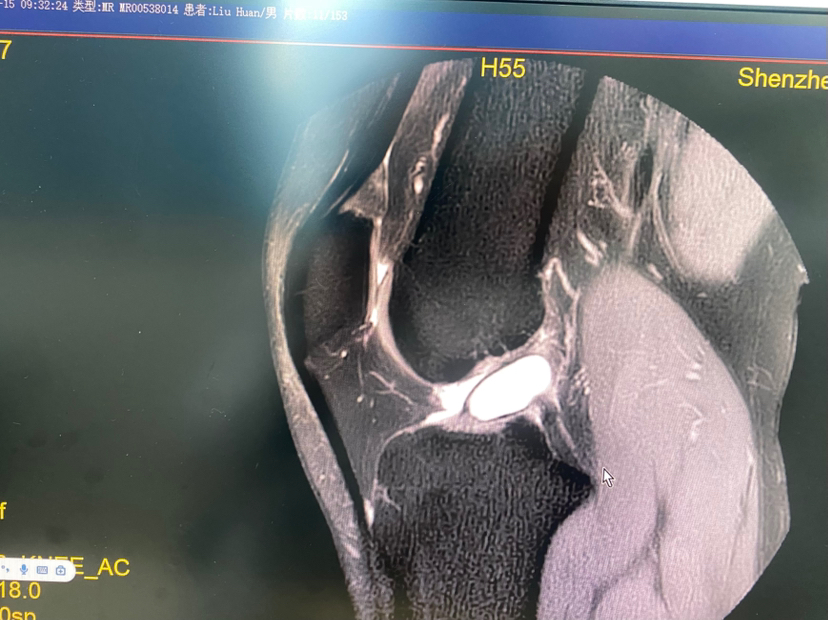

【 个别情况下韧带巨大囊肿完全或大部分侵蚀韧带,清理囊肿后,韧带纤维不多,不足以维持膝关节稳定,这种情况下需要进行韧带重建!

(囊肿巨大完全侵蚀韧带)